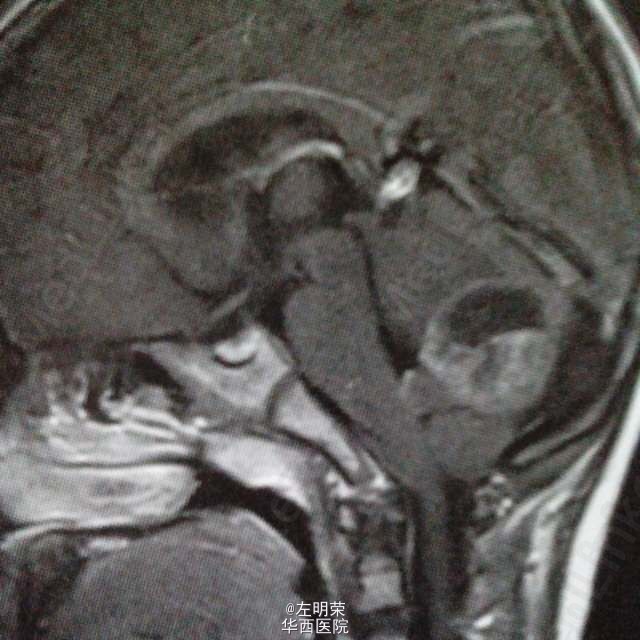

6岁小儿,主诉间断性头痛伴恶心,呕吐6天。影像特点:右侧小脑半球可见明显强化的囊实性占位,囊内可见出血后形成的液平,瘤旁轻微水肿。考虑星形细胞瘤,髓母细胞瘤,室管膜瘤可能。行手术切除治疗,见囊实性肿块,囊内坏死出血,肿瘤血供丰富,边界不清,近全切。病理结果:髓母细胞瘤